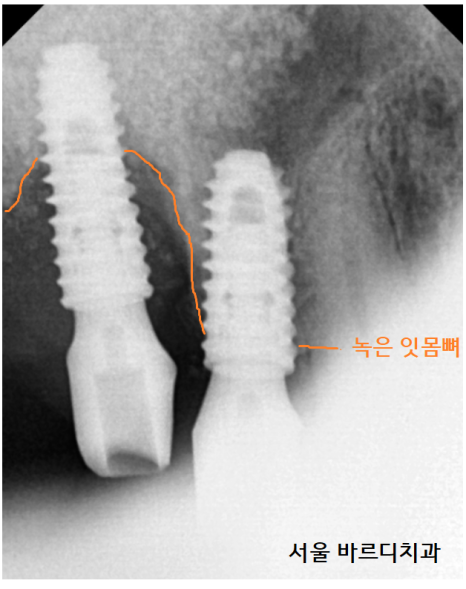

잇몸뼈가 녹아서

뽑아야 할 치아가 있었습니다.

23.02.16

다른 치과에서 심어놨던

임플란트도 제거가 필요했고요.